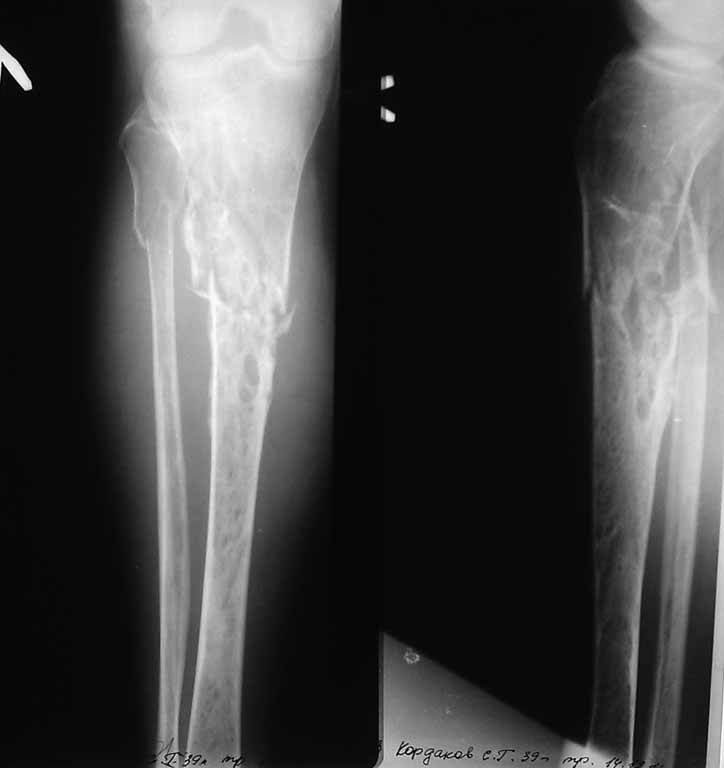

Уважаемые коллеги! Есть ли у кого опыт лечения пациентов с переломами трубчатых костей (в данном случае проксимальный метаэпифиз большеберцовой кости)при болезни Гоше? Пациент мужчина 39 лет.Диагноз:Закрытый, неосложненный, оскольчатый перелом проксимального метаэпифиза большеберцовой кости, верхней трети малоберцовой кости левой голени со смещением. Снимки прилагаются. Как вы считаете, какая тактика будет более рациональна у данного больного, учитывая его сопутствующий диагноз?